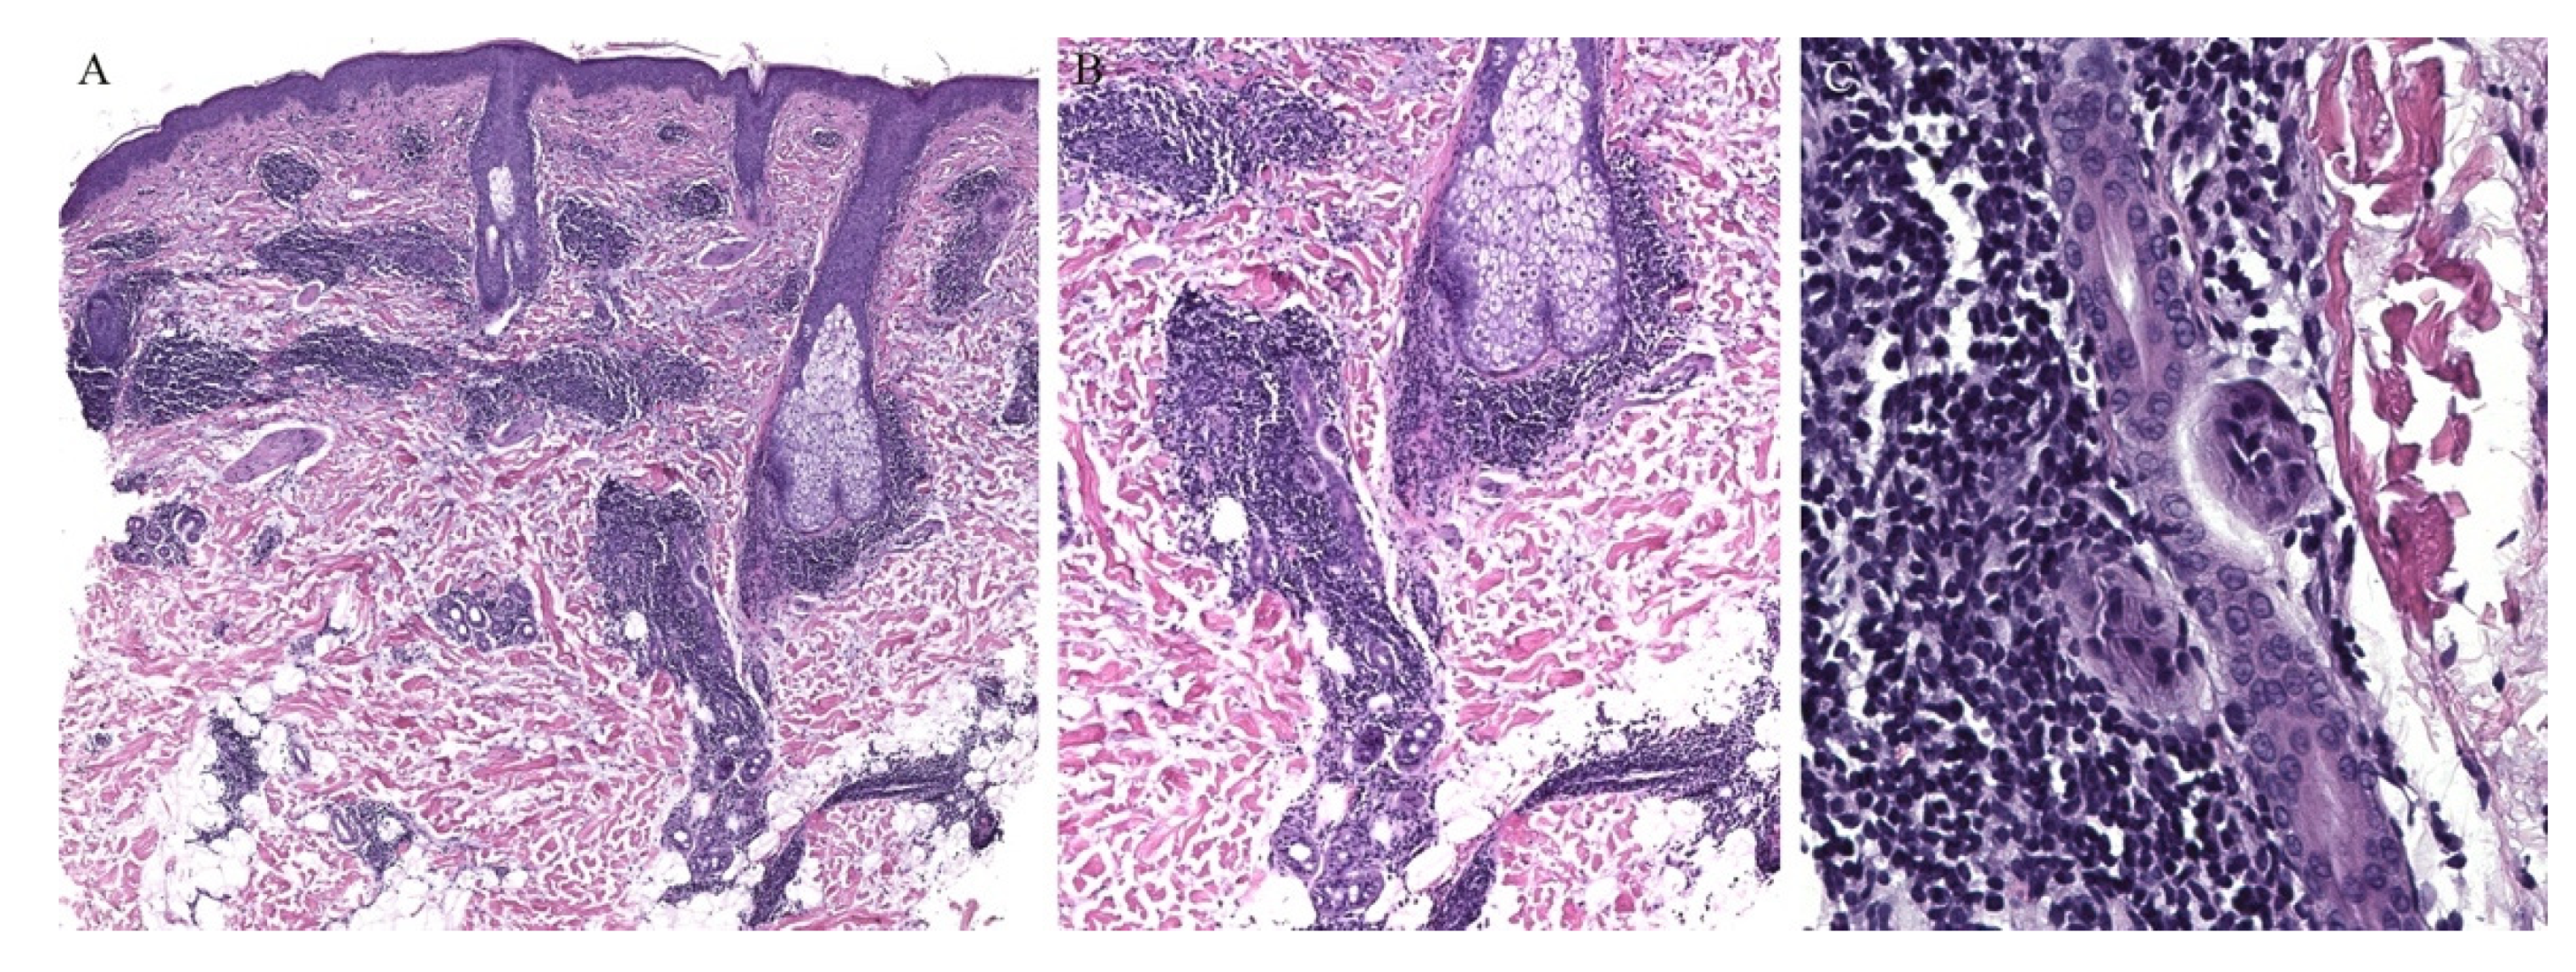

Lichen planus is the prototype lichenoid dermatitis characterized by a self-limiting eruption of pruritic flat-topped violaceous papules. On histopathology, hyperkeratosis, hypergranulosis, irregular acanthosis, and subepidermal clefts known as Max Joseph spaces are observed. A band-like lymphohistiocytic infiltrate is also seen. Distinct adnexotropic variants of lichen planus have been described (Figure 1). These include follicular lichen planus, lichen planus follicularis tumidus, and syringotropic lichen planus.

Lichen planopilaris, or follicular lichen planus, is a distinct variant of lichen planus whereby inflammation is seen around the hair follicle both clinically and histologically (Figure 1). Clinically, this presents with perifollicular erythema, follicular keratotic plugs, and a scarring alopecia [1,2].

Figure 1. (AC) Lichen planus with follicular involvement.